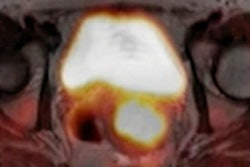

A grade 3 case (T1bN0M0, stage I) of esophageal cancer showing carbon-11 methionine radiotracer uptake on PET/CT before and three weeks after carbon ion radiotherapy. Image courtesy of Scientific Reports.The study is the first to report MET-PET/CT imaging in esophageal cancer patients and to evaluate radiotracer uptake as a parameter for detecting early response to CIRT, according to Nishii and colleagues. As such, limits included the small number of patients, they wrote.